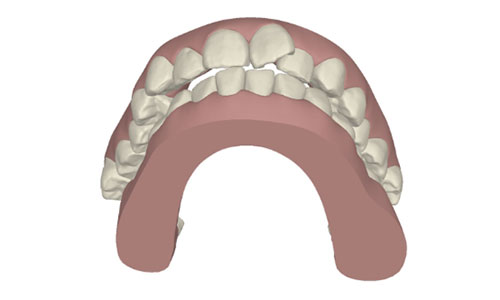

コンピューターを使って作製した透明なマウスピース型の矯正装置(アライナー)を段階的につけ替えていき、それにより歯列を矯正し、歯並びへと改善します。はじめに 治療開始から終了までのアライナーができあがってきます。マウスピース型矯正装置(インビザライン)の最大の特徴として「クリンチェック」というソフトがあります。3D のコンピュータ シュミレーション画像で、治療開始から完了までを目で見て確認することができます。

マウスピース型矯正装置(インビザライン)治療においては、クリンチェックというシミュレーションソフトを活用しております。

このクリンチェックの魅力は、治療前の現在の歯並びから治療後の歯並びを視覚化して患者様にご説明できる点にあります。

また、抜歯・非抜歯、全体矯正・部分矯正などそれぞれの治療パターンをシミュレーションすることが可能です。